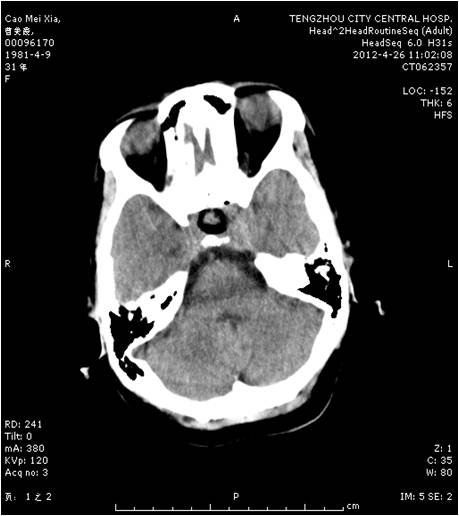

垂體瘤術(shù)前 垂體瘤術(shù)后